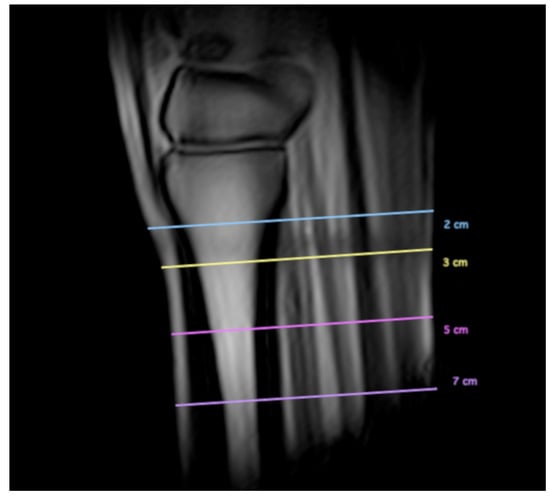

| PcMcIII 25–75% | |||||||

|---|---|---|---|---|---|---|---|

| Level | 25% | 75% | MD [mm] | p Value | 95% CI [mm] | ||

| Mean [mm] | SD [mm] | Mean [mm] | SD [mm] | ||||

| 2 cm distal to CMCJ | 3.4 | 1.0 | 2.7 | 0.8 | 0.8 | <0.01 * | 0.6, 0.9 |

| 3 cm distal to CMCJ | 4.3 | 1.1 | 3.4 | 0.8 | 0.9 | <0.01 * | 0.6, 0.1 |

| 5 cm distal to CMCJ | 4.7 | 1.0 | 4.4 | 0.8 | 0.4 | <0.01 * | 0.2, 0.6 |

| 7 cm distal to CMCJ | NNDD a | ||||||

| Differences in PcMcIII overall thickness between two different levels among the four measured levels | |||||||

| level | proximal | distal | MD [mm] | p value | 95% CI [mm] | ||

| 2–3 cm distal to CMCJ | 3.3 | 0.9 | 4.4 | 1.0 | 1.1 | <0.01 * | 0.8, 1.4 |

| 3–5 cm distal to CMCJ | 4.4 | 1.0 | 5.0 | 0.9 | 0.6 | <0.01 * | 0.4, 0.8 |

| 5–7 cm distal to CMCJ | 5.0 | 0.9 | 5.8 | 1.2 | 0.7 | <0.01 * | 0.4, 1.0 |